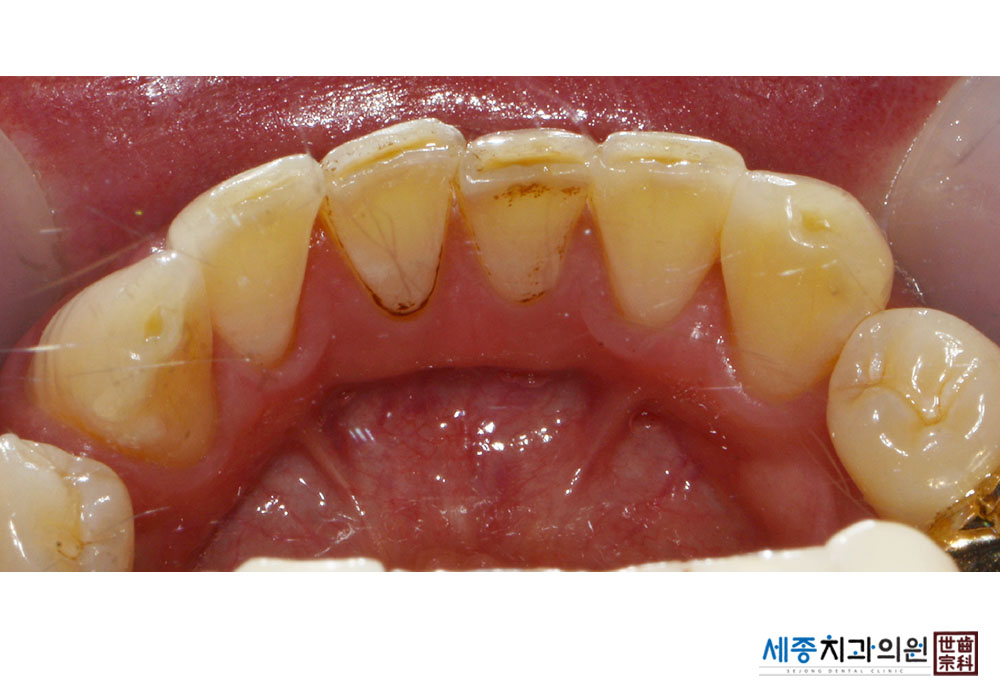

[스케일링] 치주질환 예방 스케일링

치료전 : 2022-12-01

치료후 : 2022-12-01

가글마취&저주파 스켈러를 사용한 스케일링